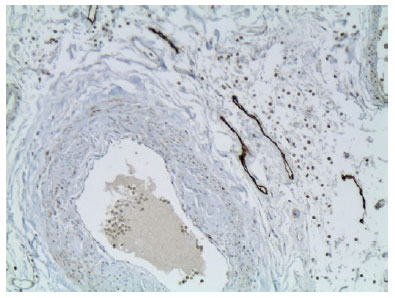

The sections of lacrimal gland (Figure 1), optic nerve (Figure 2), adipose tissue (Figure 3), and oculomotor muscles (Figure 4) stained positive for podoplanin D2-40.

02-fig03.jpg)